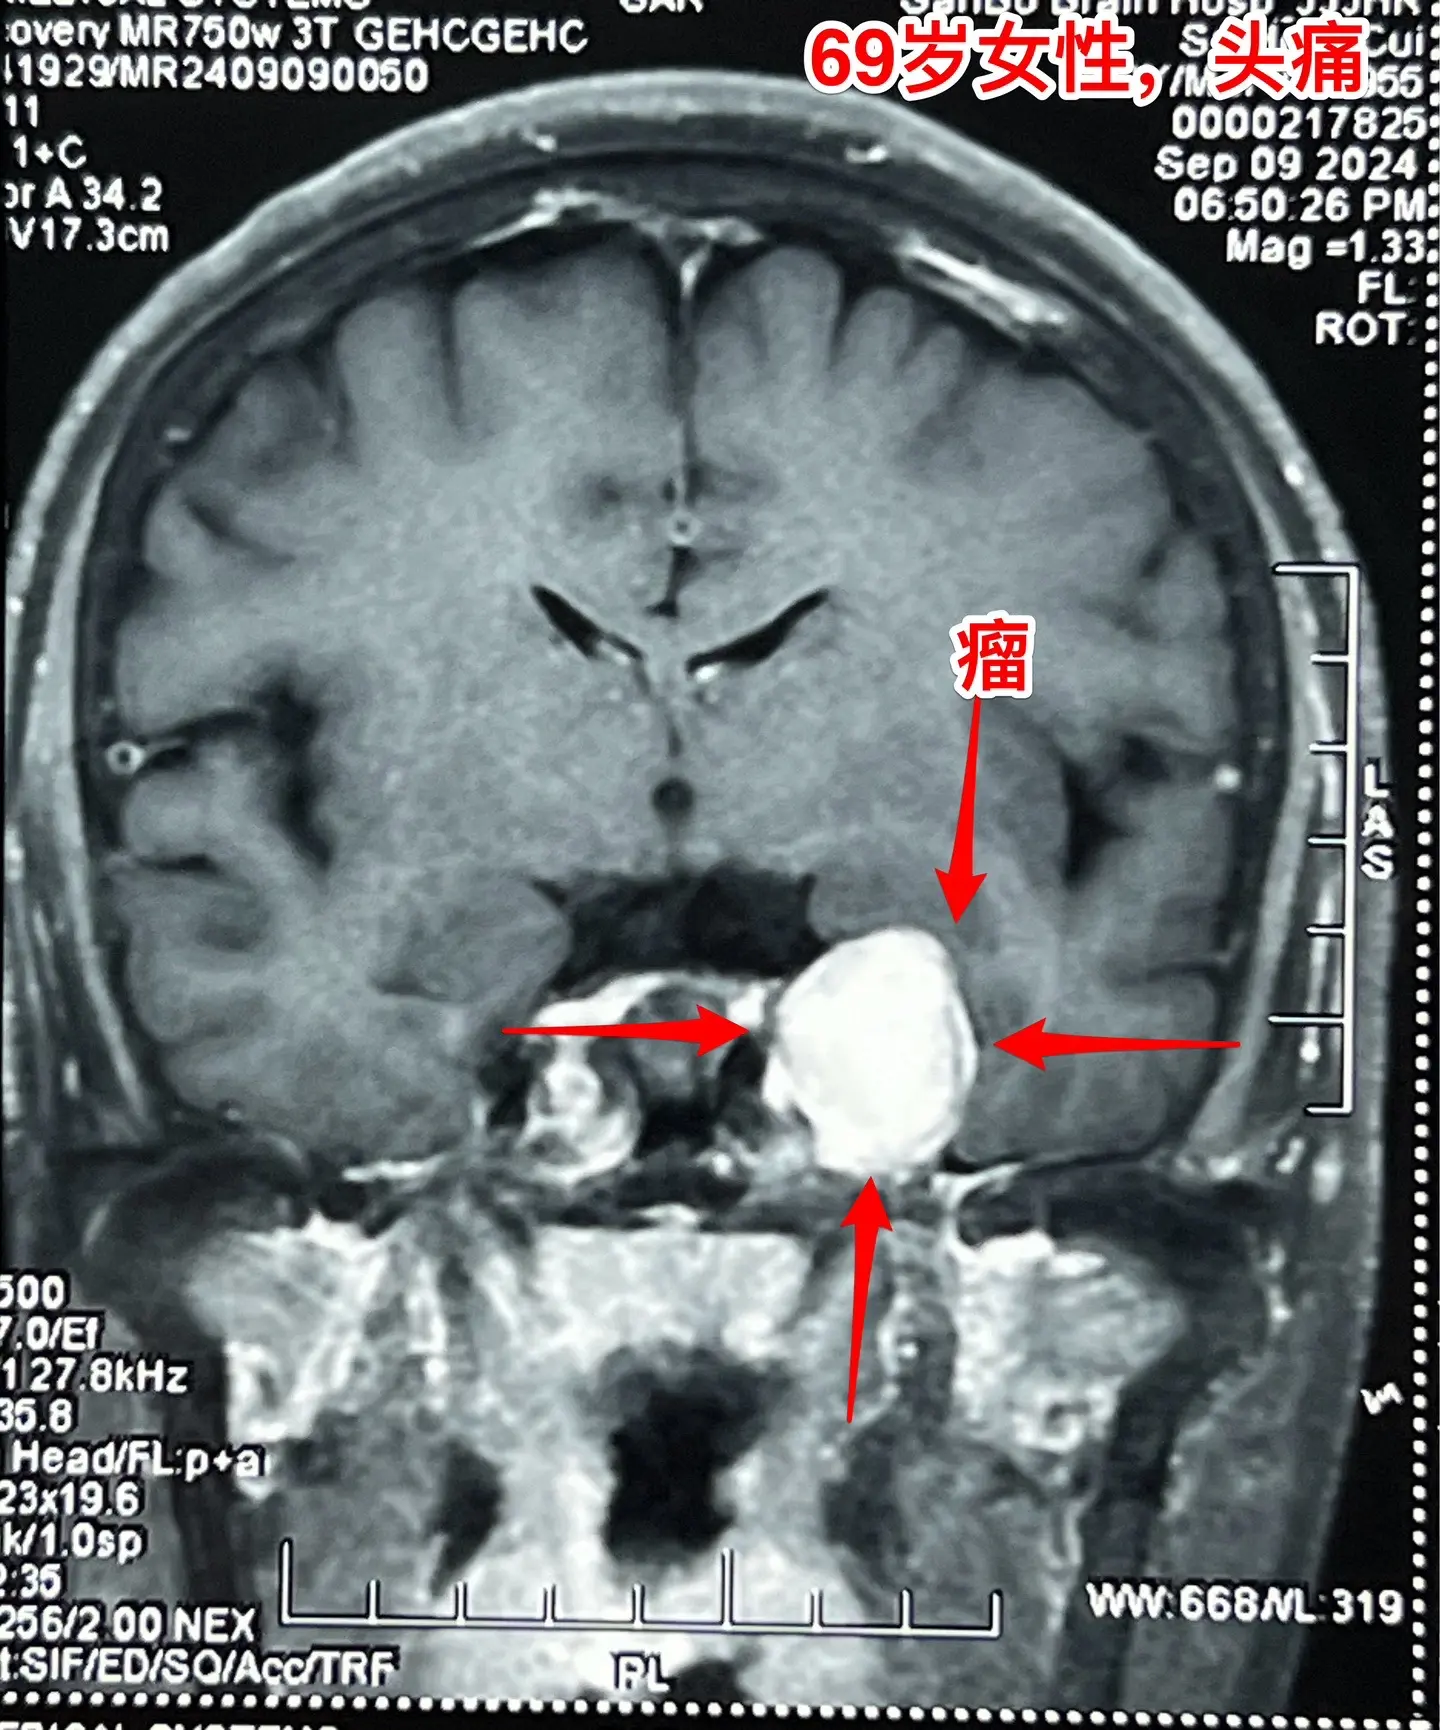

海绵窦区神经鞘瘤,是良性肿瘤。69岁青岛市老太太经常感到头痛,不太剧烈,没有专门去检查。九月份检查脑部磁共振发现左侧海绵窦长了肿瘤。在我院住院后作了强化磁共振,看见左侧海绵窦内有个大肿瘤,见图,考虑是神经鞘瘤,神经鞘瘤是良性肿瘤,如果完全切除了就可以治愈。 老太太有两个女儿,积极要求给她作手术。69岁年龄还是有点大,手术是有风险的! 9月12日下午四点开始进入手术室,手术持续到13日凌晨才结束。手术过程很顺利,肿瘤得到完全切除。今天看见老太太精神比较好,准备下地行走。神经鞘瘤海绵窦